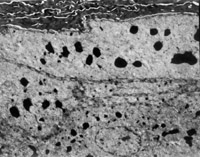

2. 電鏡觀察 受傷當日上皮組織變性壞死,可見單核細胞核偏移、固縮,并有吞噬現(xiàn)象(圖5-3-12)。

5-3-12 燒傷當日,單核細胞核偏移,固縮,并有吞噬現(xiàn)象  TE×8000